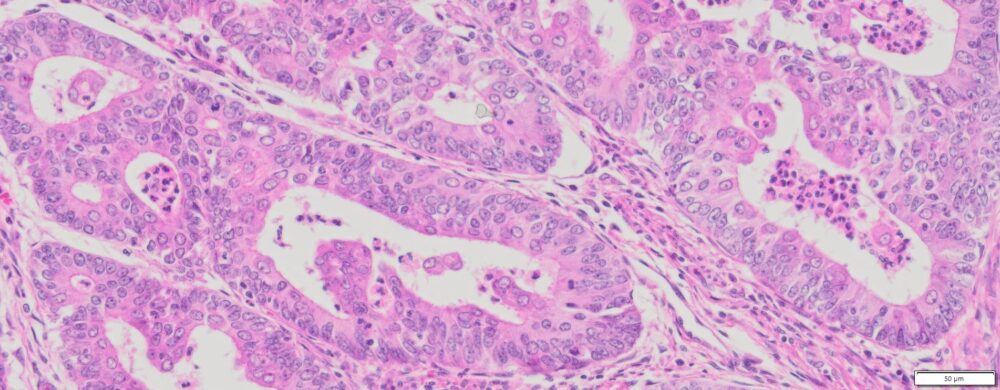

Description

| Organ& Tissue | Pathology Diagnosis | Gender/Age | % Tumor Area | Grade | TMN Stage | Biomarkers |

| Endometrial | Moderately differentiated endometrioid adenocarcinoma of the endometrium | Female/70 | 40% | 2 | T1bNxMx |